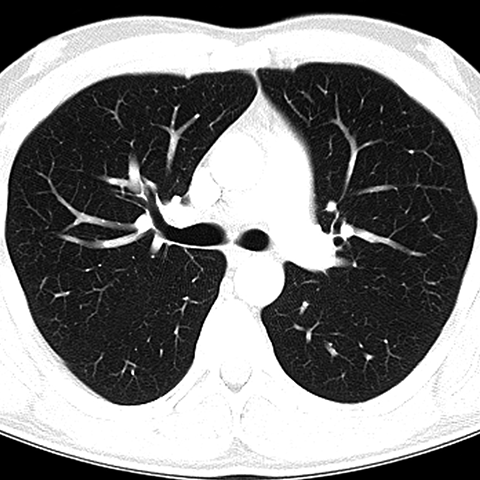

CT of Normal Trachea and Bronchi [3 of 5]